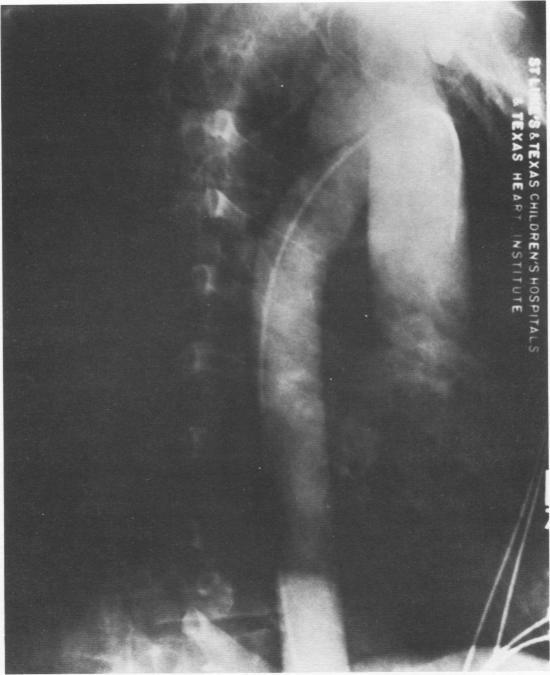

Between 1957 and 1983, 58 patients were treated in our institution for traumatic rupture of the thoracic aorta. Seven patients had acute ruptures and 51 had traumatic aneurysms. Surgical correction of the lesion was obtained by means of left femoral artery bypass in 17 patients, femoral artery-femoral vein bypass in five patients, and external shunt in three patients. After 1975, simple aortic cross-clamping was used in 33 patients. There was one death 1 week after a procedure for ventricular fibrillation. Paraplegia occurred in two patients, and both cases were correlated with hypotensive episodes. From this experience and that of others, it was determined that an aortogram should be performed in all patients suspected of having highspeed deceleration trauma, and that such patients should undergo surgical repair as soon as possible after diagnosis.

1957年至1983年间,我院共收治58例胸主动脉创伤性破裂患者。其中7例为急性破裂,51例为创伤性动脉瘤。17例患者通过左股动脉旁路手术进行病变的外科矫正,5例患者采用股动脉-股静脉旁路手术,3例患者采用体外分流术。1975年后,33例患者采用单纯主动脉交叉钳夹术。有1例患者在手术后1周因心室颤动死亡。2例患者发生截瘫,均与低血压发作有关。根据这一经验以及其他经验,确定所有怀疑有高速减速创伤的患者均应进行主动脉造影,且此类患者在诊断后应尽快接受手术修复。